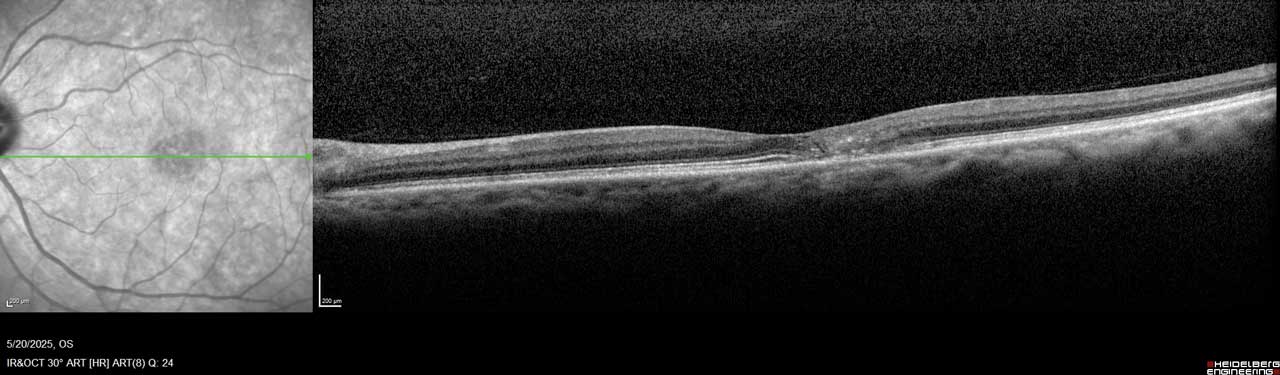

Figure 2. Imaging of the left eye of this MacTel patient shows flattening of the temporal foveal pit, hyperreflective middle retina layers, and loss of outer retinal signals, including photoreceptors temporal to the center of the macula.

MacTel is believed to result from degeneration of Müller cells, the glial cells that surround and support neurons in the retina. This neurodegeneration leads to outer retinal atrophy and thinning, ultimately resulting in photoreceptor loss. In later stages, hyporeflective spaces in the outer retinal layer—most often within the foveal pit—can be observed on optical coherence tomography (OCT), indicating photoreceptor loss (Figure 1 and Figure 2).¹